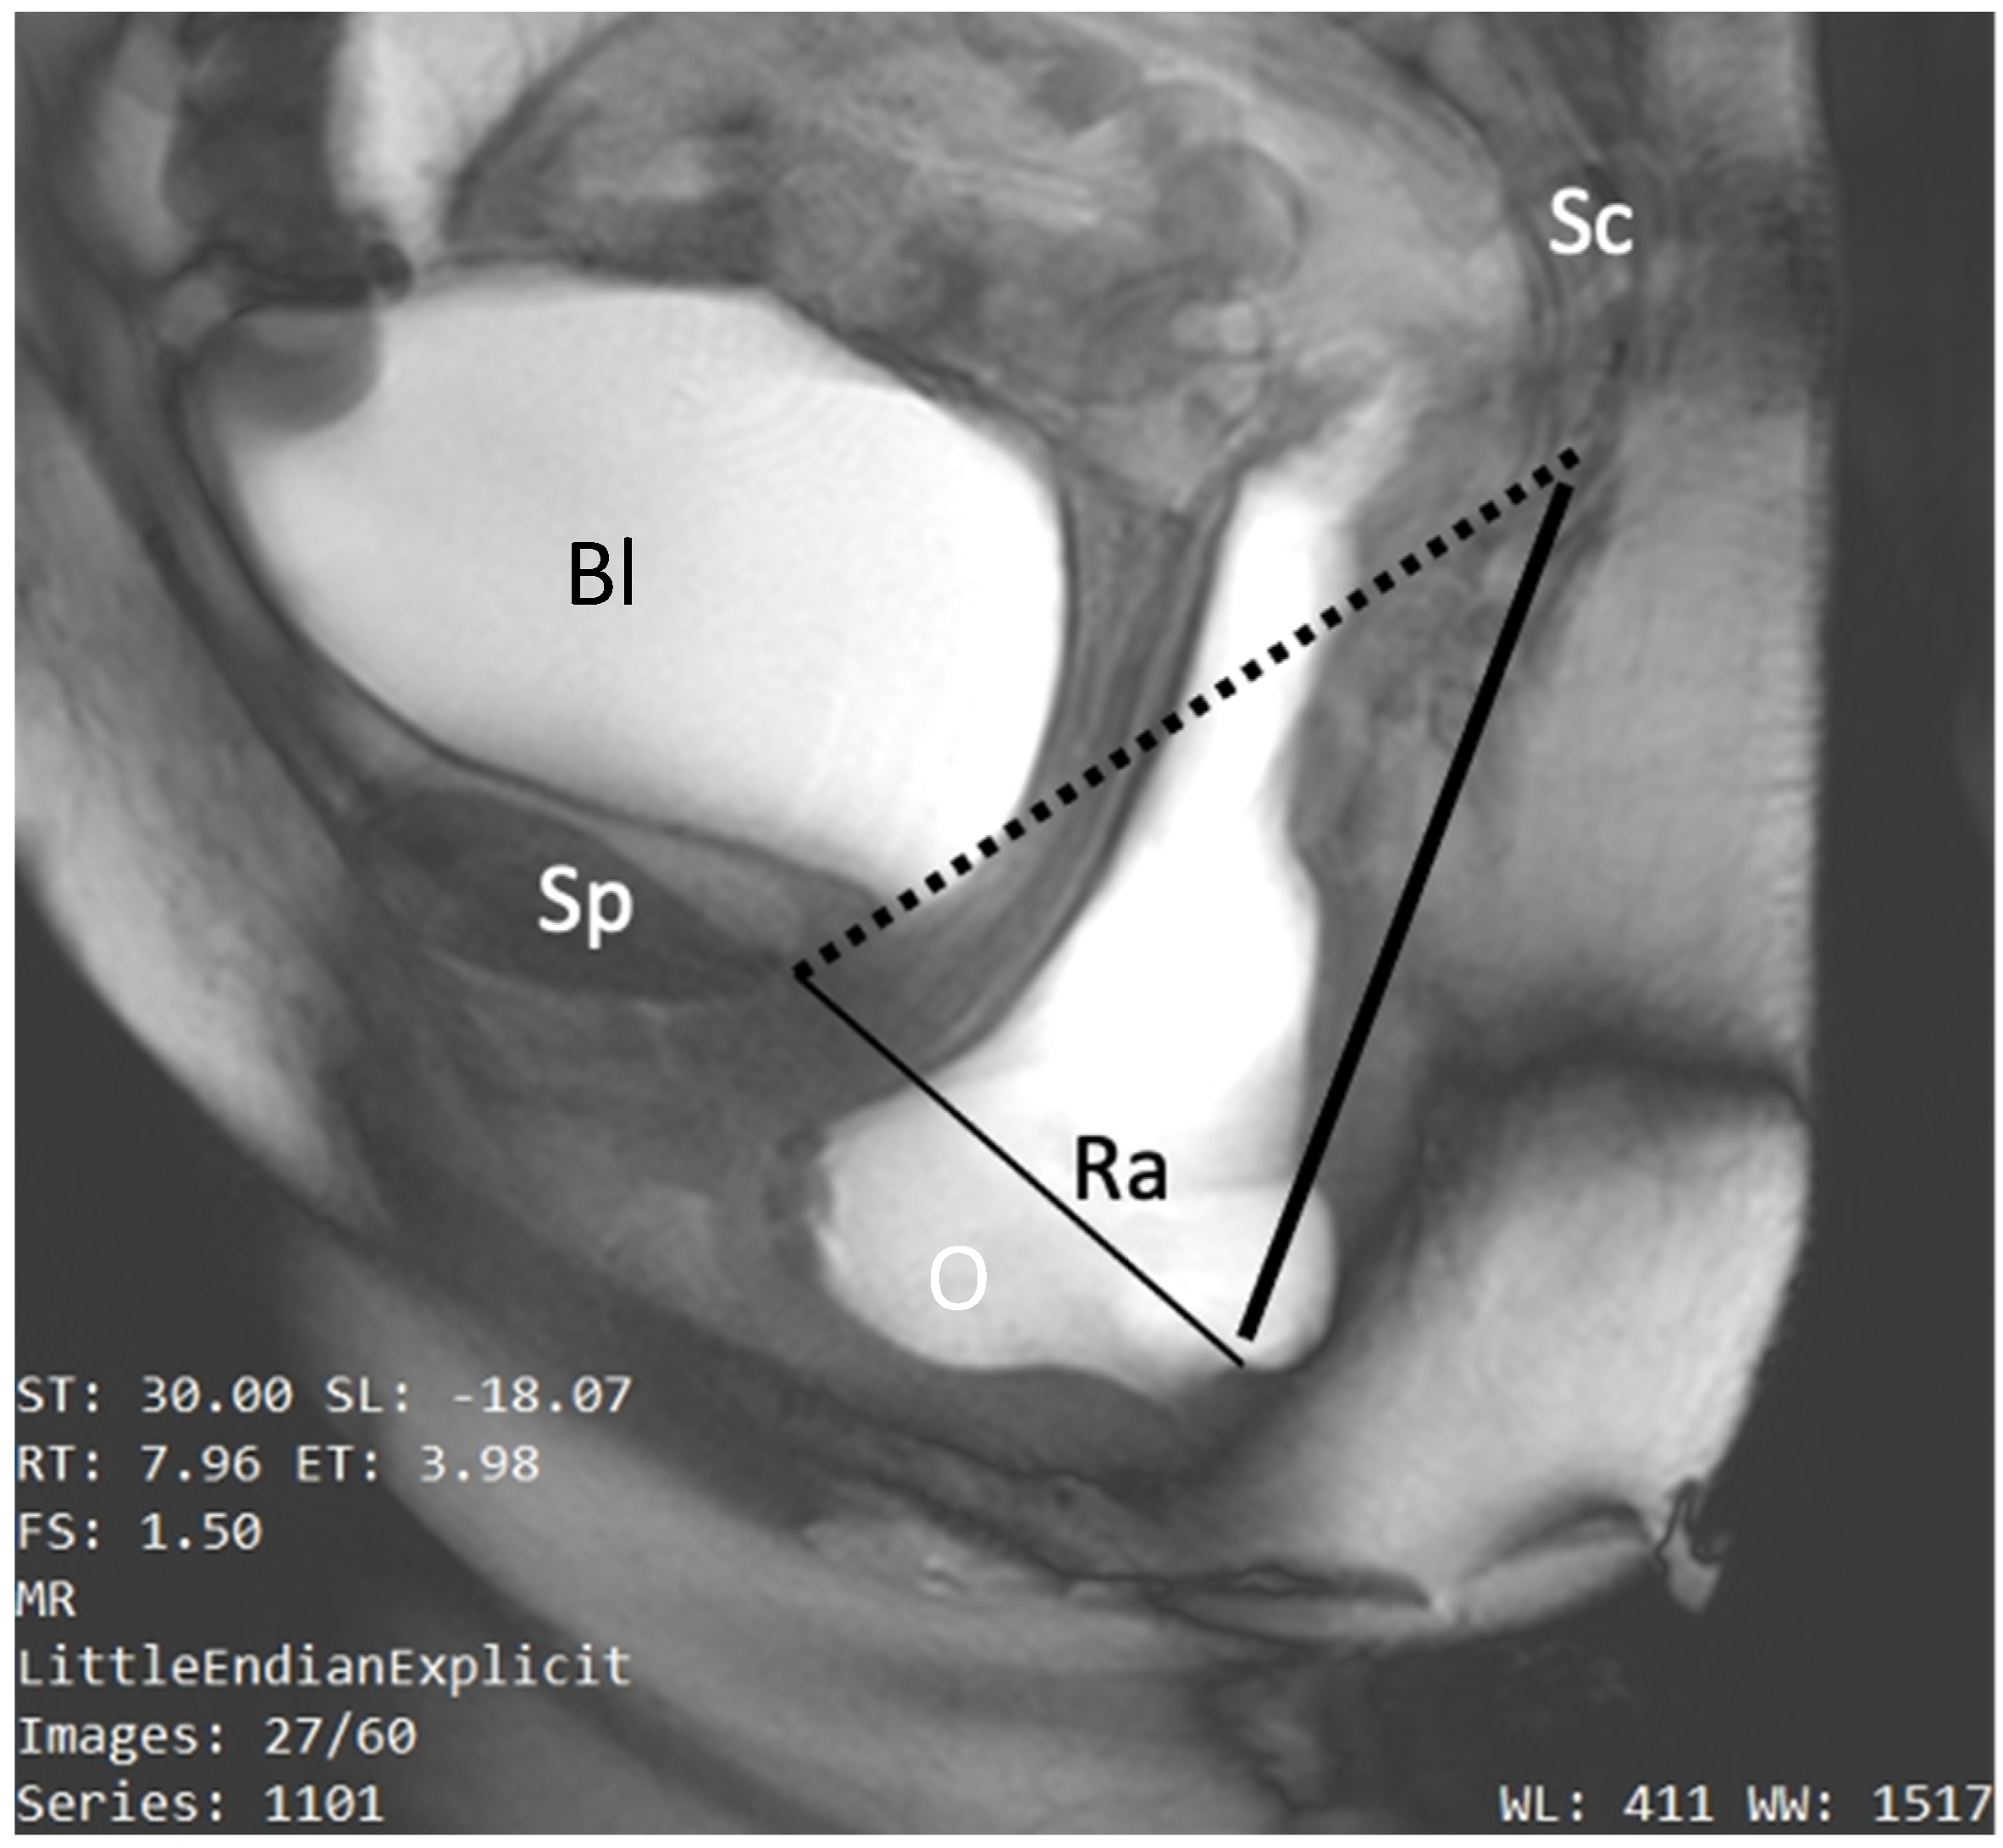

5.2.5. The Pubococcygeal Line (PCL)

5.2.6. The HMO Classification System

- Pelvic organ descent: defined as the difference between the resting and straining positions of the bladder neck, prostate base, vaginal vault, and anorectal junction (ARJ). This descent is measured relative to a reference line (PCL or horizontal line) and indicated by a number preceded by a minus sign (−) for above or a plus sign (+) for below the reference. Normal values are −3 cm for the bladder base, prostate, and vaginal vault and −2 cm for the ARJ.